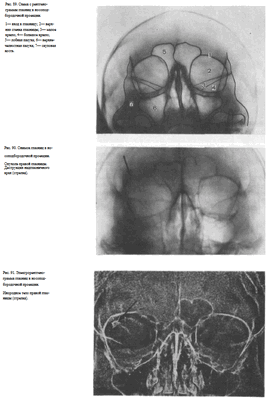

УКЛАДКИ СНИМОК ГЛАЗНИЦЫ В НОСОПОДБОРОДОЧНОЙ ПРОЕКЦИИ

Назначение снимка. Изучение состояния костей, образующих вход в глазницу, костной структуры верхней и наружной ее стенок.

Укладка больного для выполнения снимка сходна с укладкой для выполнения обзорного снимка в этой же проекции. В данном случае используюткассету размером 13X18 см, располагая ее в кассетодержателе в поперечном положении. Больной прилежит к столу подбородком и кончиком носа,переносье соответствует центру кассеты. Центральный пучок излучениянаправляют на центр кассеты. Фокусное расстояние—100 см.

В этой же укладке может быть выполнен снимок одной (правой или левой) глазницы. В таких случаях центр снимаемой глазницы соответствует центру кассеты, и на него отвесно направляют пучок излучения, используя тубус или диафрагмирование пучка излучения с помощью щелевой диафрагмы. Фокусное расстояние—100 см (рис. 88).

Информативность снимка. На снимке хорошо видны вход в глазницу, структура ее стенок, иногда малое и большое крыло клиновидной кости (рис. 89). На снимке в этой проекции могут быть выявлены деструктивные изменения стенок глазницы и инородные тела в ее полости (рис. 90, 91). Для выявления изменений в области верхней стенки глазницы (например, при

диагностике переломов) снимок целесообразно выполнять не в носоподбородочной, а в подбородочной проекции.

На таких снимках верхняя стенка глазницы проекционно искажается в меньшей степени, и все изменения в ее области видны более отчетливо (см. рис. 54, 55).

На прицельном снимке каждой из глазниц в этой же проекции, как правило, небольшие изменения структуры стенок, а также мелкие инородные тела глаза видны лучше. Такие снимки широко используют в офтальмологической практике (рис. 92).

Критерии правильности технических условий съемки и правильности укладки основываются на четкости выявления костной структуры и симметричности изображения глазниц.

Наиболее частые ошибки при выполнении снимка сводятся к асимметрии положения головы.